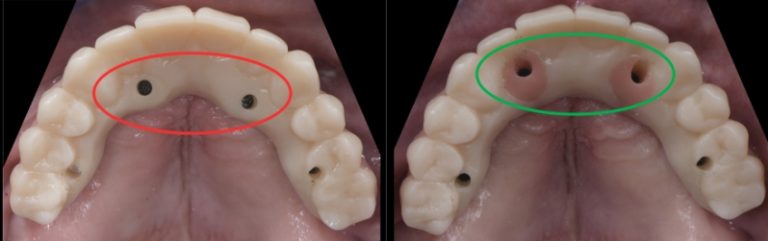

Getting the SRA Abutment Right in Implant-Supported Restorations

Dr. Ricardo Mitrani explains how altering the angle of an SRA abutment can optimize screw access design when fabricating certain…By Ricardo Mitrani